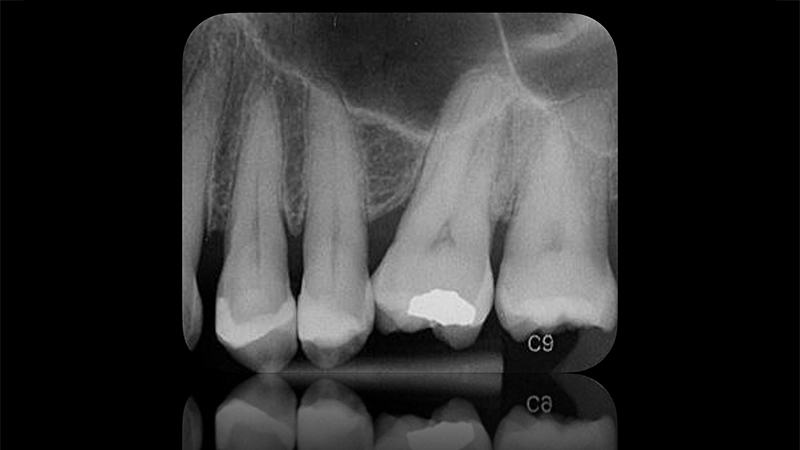

radiografia dopo il follow-up ad un mese di distanza

Fig. 18 - L'indagine radiografica mostra l'assenza di radiolucenza apicale dei due premolari e, pertanto, la vitalità della polpa è stata mantenuta dopo il follow-up ad un mese di distanza.